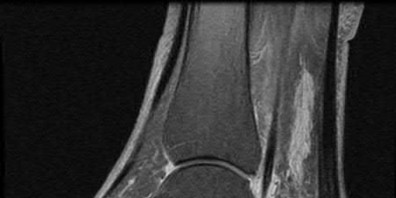

A 40-year-old male sustains a high-energy Pilon fracture. Initial treatment consists of a spanning external fixator across the ankle joint. Which of the following clinical findings best indicates that the soft tissue envelope has recovered sufficiently to permit definitive open reduction and internal fixation (ORIF)?

Correct Answer: Return of the 'wrinkle sign' on the anterior ankle skin

Explanation:

In the staged management of high-energy Pilon fractures, definitive ORIF must be delayed until the soft tissue envelope has adequately healed to minimize the risk of wound complications and infection. The return of skin wrinkles (the 'wrinkle sign') indicates a significant reduction in interstitial edema and is the widely accepted clinical milestone for proceeding with definitive fixation, typically 10 to 21 days post-injury.